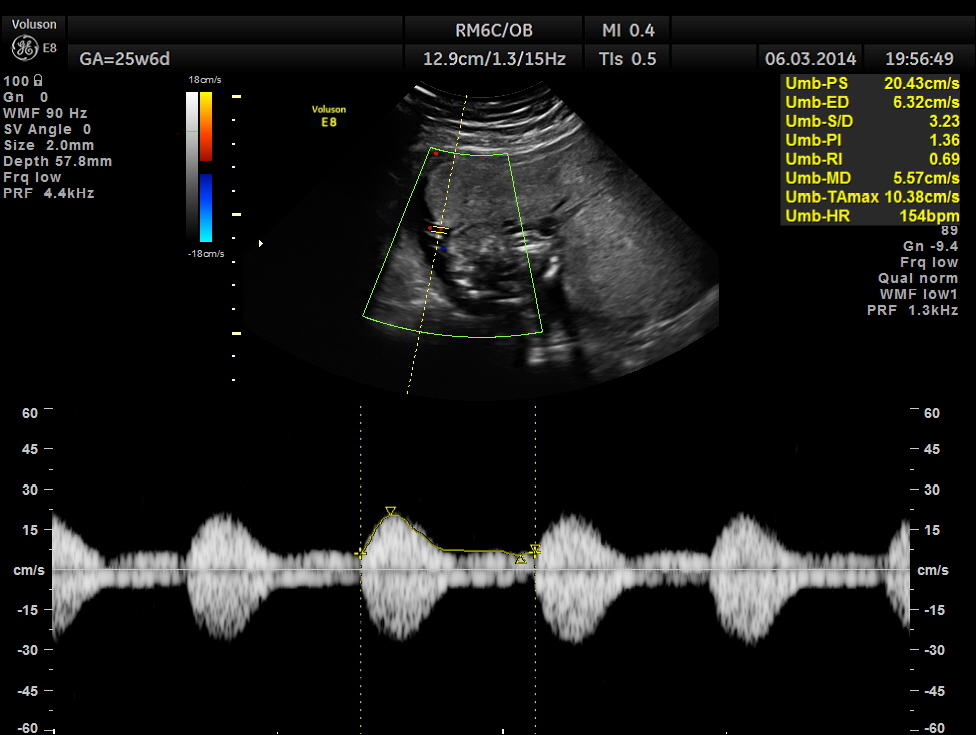

The GA was around 25 weeks , but the AUA was around 19 to 20 weeks. All parameters – BPD, HC, AC, FL are < 2.3 %tile and all other long bones are < 5.0 %tile.

Umbilical arterial P.I. and R.I. are higher for the GA.